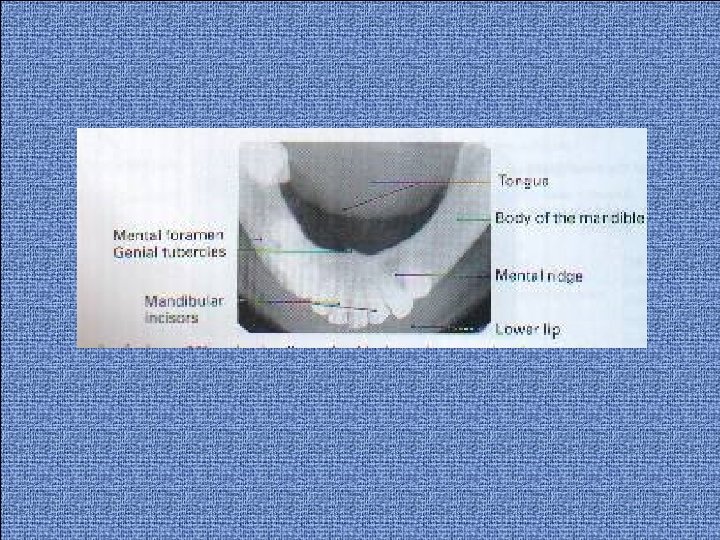

Mandibular occlusal projections: (Fig. 46 Lower 90 o occlusal (true). Lower 45 o or anterior occlusal (standard). Lower oblique occlusal.

Lower 90 o occlusal The image receptor facing downwards is placed centrally into the mouth, on the occlusal surface of the lower teeth, with long axis crossways. The patient is asked to bite together gently. If wanted to examine other part of mandible, the image receptor is placed with its long axis anteroposeriorly over the area of interest. The patient then leans forwards and then tips the head backwards as far as is comfortable, where its supported. The X-ray tubehead with circular collimator fitted is placed below the patient's chin in the midline centring on an imaginary line joining the 1 st molars at angle of 90 o to the image receptor.